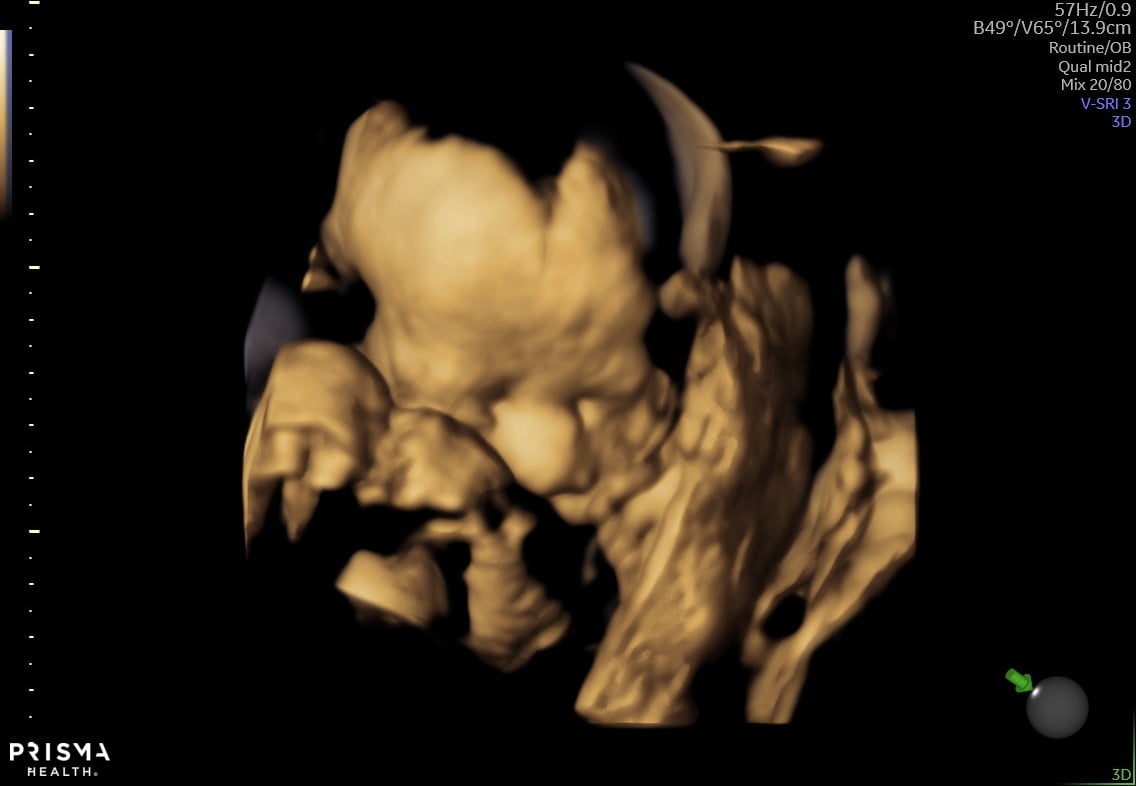

Had a private ultrasound today at 15+1 and we’re having baby boy #3!!! I’m so excited, we have everything and I love being a boy mom! He even waved at us during our ultrasound!